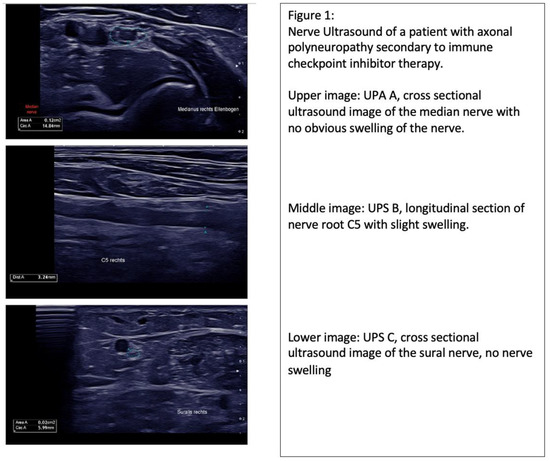

| 1 | M | 41 | 13 UPS A 7 UPS B 3 UPS C 3 |

| 2 | M | 86 | 17 UPS A 13 UPS B 3 UPS C 1 |

| 3 | F | 62 | 20 UPS A 13 UPS B 3 UPS C 4 |

| 4 | M | 84 | 11 UPS A 8 UPS B 1 UPS C 2 |

| 5 | M | 65 | 6 UPS A 4 UPS B 2 UPS C 0 |

| 6 | M | 69 | 15 UPS A 11 UPS B 2 UPS C 2 |

| 7 | M | 52 | 8 UPS A 6 UPS B 2 UPS C 0 |

| 8 | F | 71 | 6 UPS A 3 UPS B 2 UPS C 1 |

| 9 | F | 75 | 7 UPS A 3 UPS B 3 UPS C 1 |

| 10 | F | 45 | 15 UPS A 12 UPS B 2 UPS C 1 |